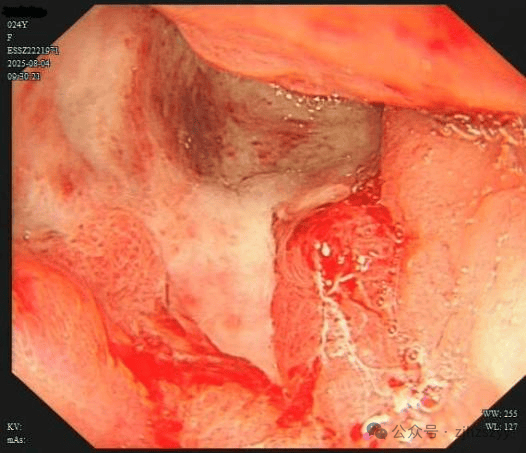

直到她开始频繁出现黑便,并在片场拍戏时几次呕血,才被同事紧急送往医院急诊。情况紧急,医生立即为小雯安排了急诊胃镜检查,发现她整个胃窦被一巨大的溃疡占据,黏膜组织变得僵硬、缺乏弹性,好似“皮革”一般。而随后的活检结果,更是给了这个年轻姑娘沉重一击——胃印戒细胞癌。